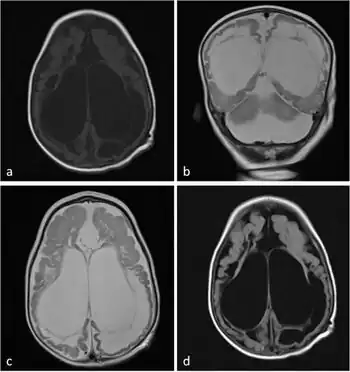

Diagnosis of molybdenum cofactor deficiency includes early seizures, low blood levels of uric acid, and high levels of sulphite, xanthine, and uric acid in urine. Additionally, the disease produces characteristic MRI images that can aid in diagnosis.[4]